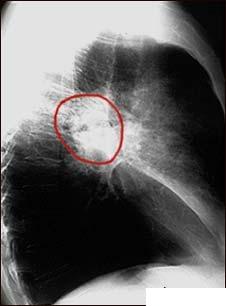

Hemoptizia (expectoratia cu sange)